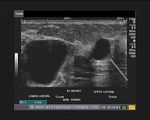

This ultrasound image shows prominent and dilated mammary ducts in the lactating breast. The ducts are seen as tubular hypoechoic structures, which widen as they approach the nipple. Sometimes, it may be possible to see fat drops within the milk secretions in the ducts. These appear as mildly echogenic debris within the ducts. Image taken using a Toshiba Nemio 30 ultrasound scanner, courtesy of Dr. Vikas Arora, India.